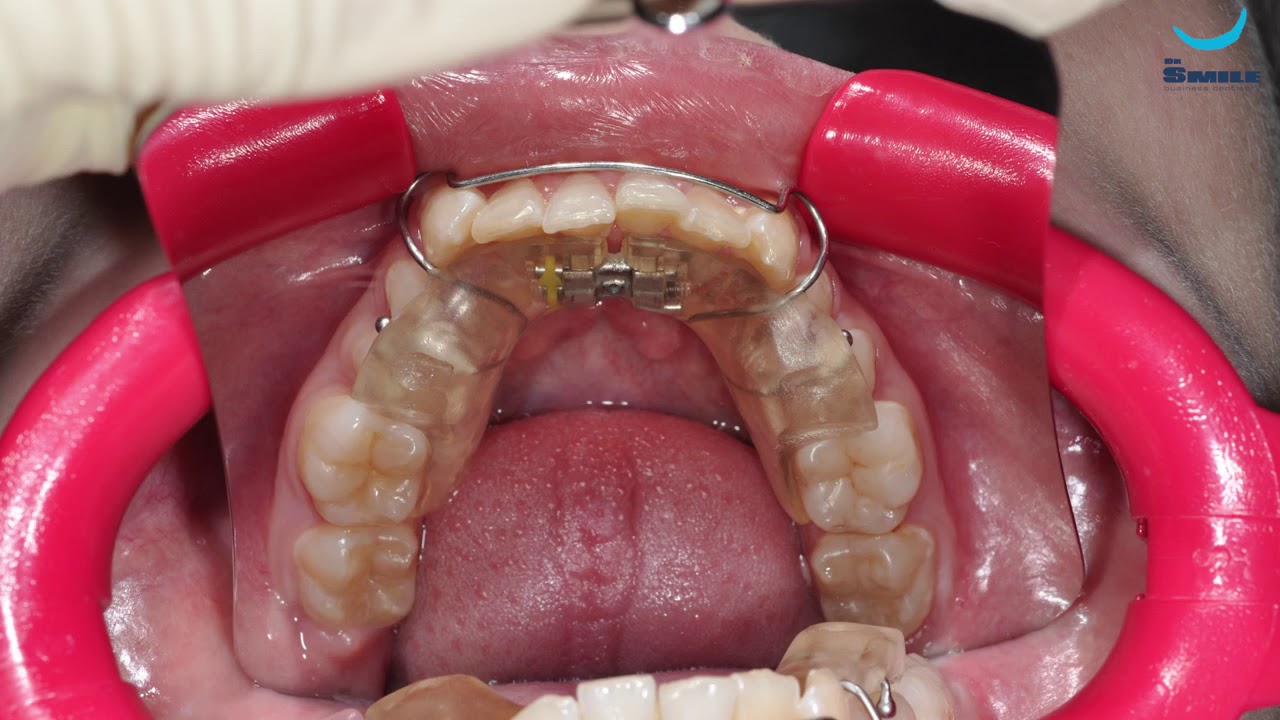

From www.youtube.com

Установка брекет системы. Врач Догару А. М. dr Smile YouTube Harga Braces Dr Smile Have you ever thought that someone’s natural smile looked better after having braces? Dr smile kostet zwischen 1.790 und 3.990 €, aber sie können 150 € rabatt auf ihre behandlung erhalten, wenn sie heute mit unserem rabattcode dentalysmile150 einen unverbindlichen infotermin buchen. Harga paket pasang behel ini sudah termasuk dengan biaya. Dr clear aligners, the leading provider of premium, customized. Harga Braces Dr Smile.